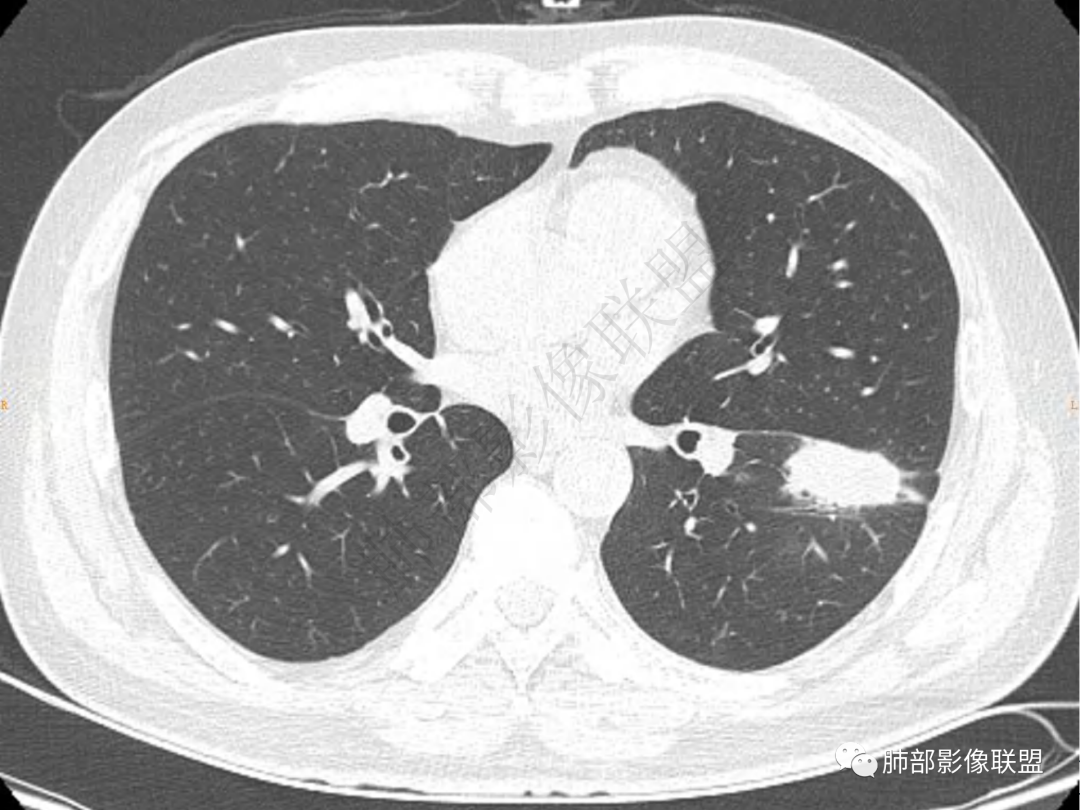

1.中年男性,咳嗽咳痰20余天,间断咯血2周

2.左肺下叶团片影,跨背段及内前基底段,实性部分类椭圆形,密度不甚均匀,可见毛刺及棘状突起,未见典型分叶及胸膜凹陷。病灶上下缘可见相应肺段支气管旁进侧出,管壁轻度增厚,未见狭窄阻塞。

3.周边较大范围磨玻璃影,边界相当模糊,小叶增厚明显。注意叶裂另一侧、左肺舌段亦可见磨玻璃影及增厚的小叶间隔。未见明确卫星病灶。

4.实性部分不均匀环形强化并显示一小范围低密度坏死区或空洞。较之肺窗,整体纵隔窗范围较小,提示病灶并不十分密实。抑或为不同时段图像。

5.双肺门及纵隔未见增大淋巴结。未见胸腔积液。

1.病灶不够密实,没有典型分叶,收缩乏力等,支气管未见截断等,缺乏一般肿瘤性肿块特征。

2.周围磨玻璃影边界不清缺乏限制,甚至“激惹”到相邻肺叶,也许提示较明显的炎性水肿。

正如多数老师分析到的,本例病灶炎性特点比较明显。